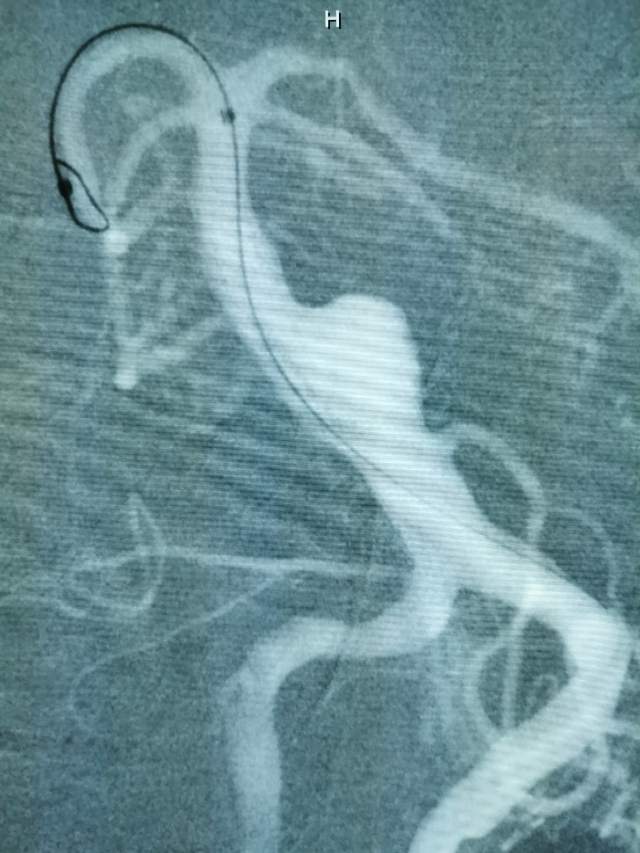

患者男性,34岁,年前自新疆坐车48小时来到我院,诊断:椎基底动脉冗长扩张症,出现脑干压迫症状、后组颅神经症状、部分中组颅神经症状、小脑症状、颅内压增高(220mmHg),症状进行性加重,最大径15mm,血管外面存在血栓造影只能窥见部分,短短两周,病变形态出现明显变化,局部出现明显瘤样凸起(图2-3),手术方案只能临时改变,植入血流导向装置,术后看病人语言、四肢活动均正常,围手术期仍然是一个艰巨的过程,充满了不确定因素,希望患者能安全度过围手术期,早日康复,重返工作岗位~~~